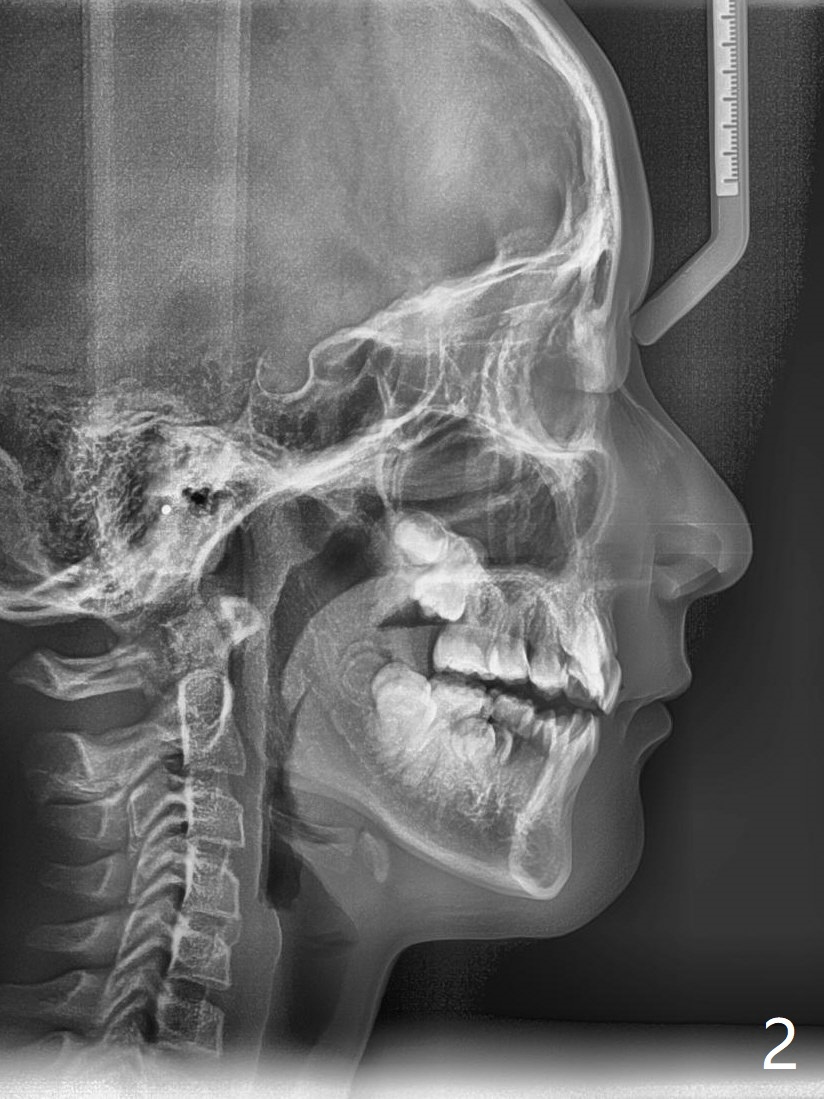

A 10-year-8-month-old woman presents to clinic with severe crowding (especially at the canines, Fig.1), but her facial profile is within normal limit (Fig.2,3) in spite of the fact that cephalometric tracing shows bimaxillary protrusion (Fig.4). Will 4 bicuspids' extraction affect her profile? Her mom requests immediate treatment, although the patient's oral hygiene is questionable.